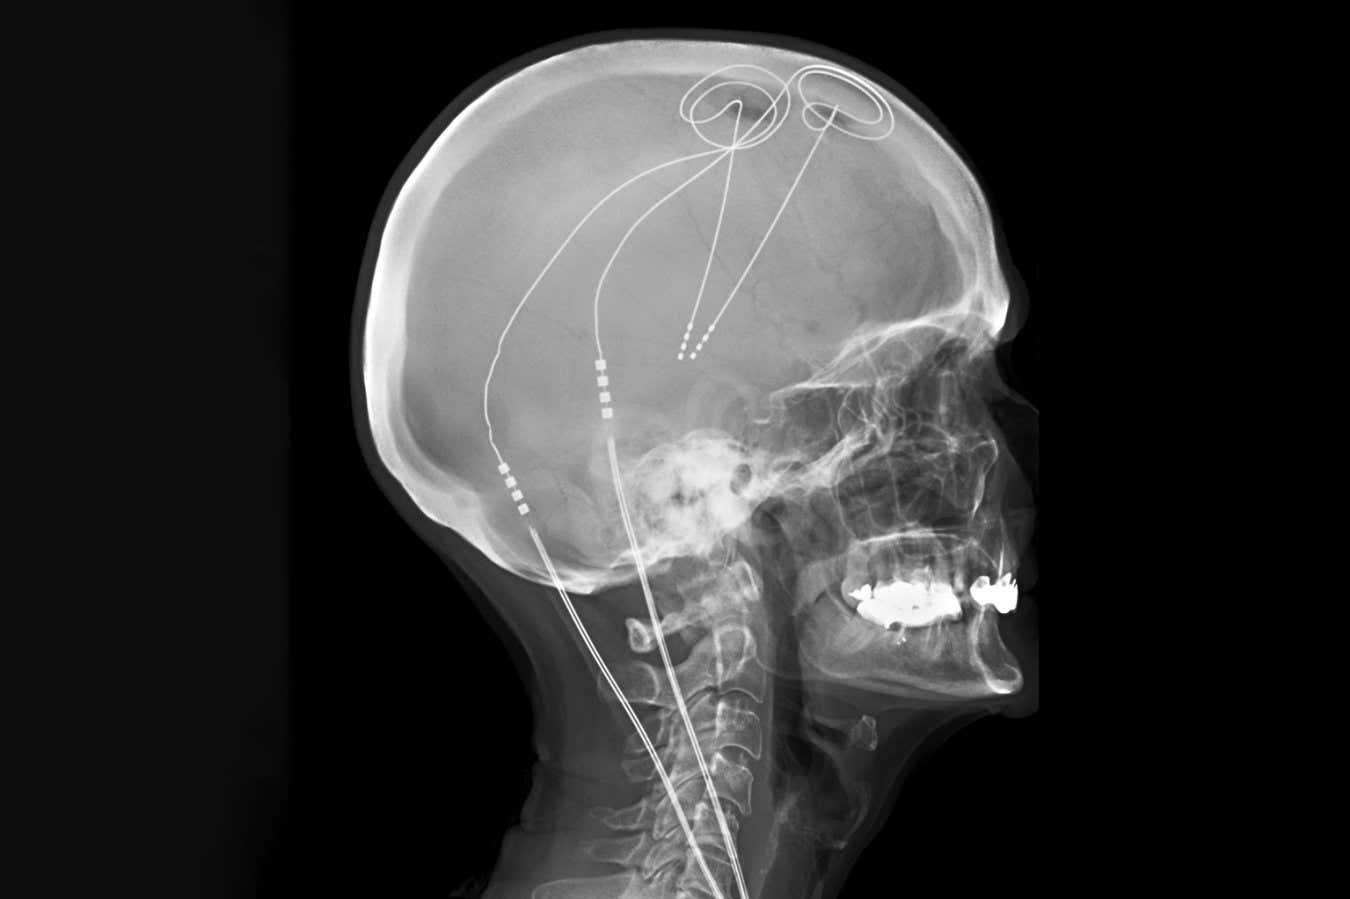

Deep brain stimulation is already used to treat Parkinson’s disease

Deep brain stimulation (DBS), which involves stimulating the brain using tiny electrodes, has shown promise but has inconsistent results. Traditionally, the same brain areas are targeted in a one-size-fits-all approach, despite evidence suggesting that pain arises from different circuits in different people.

The researchers next used machine learning to identify and distinguish between the electrical activity that occurred when the individuals experienced high or low levels of pain. They then implanted permanent DBS electrodes into each participant, which were personalised to monitor their brain activity and deliver optimal stimulation whenever pain-related activity was detected, and to deactivate when they were asleep.